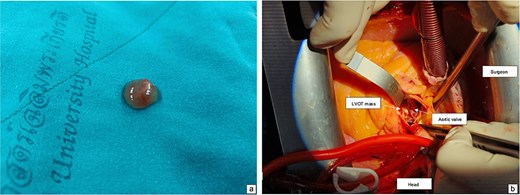

The patient underwent surgical excision of the LVOT mass via a median sternotomy. Cardiopulmonary bypass (CBP) was established using arterial cannulation in the ascending aorta and single, two-stage venous cannulation via the right atrium. An oblique aortotomy was performed to access the LVOT, and the mass was completely excised. The aorta was closed with 4–0 Prolene, and the excision site was inspected to ensure no residual tissue. Hemostasis was achieved, and CBP was weaned off once adequate cardiac function was confirmed. Two tube drainages in pericardial and mediastinal spaces. The pericardium was closed, with a total CBP time of 45 min, an aortic cross-clamp time of 27 min, and a total operative time of 3 h and 12 min. Gross pathology showed a 1 × 1 × 0.3 cm irregular, soft, grey-white polypoid mass. Histology examination of the mass revealed multiple branching papillary fronds with a central avascular collagen, lined by a layer of hyperplastic epithelial cells, consistent with papillary fibroelastoma (Figs 3 and 4).

Intraoperative view showing mass attached to the left ventricular outflow tract (a). A gross specimen of the excised mass (b).